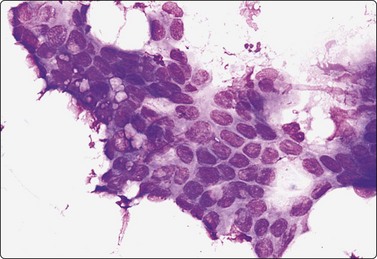

image

Fig. 13.7 Moderately-differentiated adenocarcinoma

Cellular smears of less cohesive malignant glandular epithelial cells; vesicular nuclei; prominent nucleoli. Note fragile vacuolated cytoplasm suggestive of a clear cell pattern in B (A, Pap; B, DQ, HP).

Moderately-differrentiated carcinoma (Figs 13.6, 13.7)

Microacini showing frank nuclear atypia,

Frequent obviously malignant irregular three-dimensional clusters,

Nuclear hyperchromasia,

Conspicuous nucleoli,

Some dissociated well-preserved malignant cells,

The smear may be overrun by malignant irregular three-dimensional clusters.

In smears of prostatic carcinoma, sheets of benign glandular epithelial cells are commonly seen side-by-side with aggregates of malignant cells (Fig. 13.6), reflecting the diffusely infiltrative growth of the tumor. Benign and malignant cells can be directly compared (very helpful clue) and differences in cytoarchitectural features are easily appreciated. Nuclear enlargement is one of the most important criteria of malignancy. Nucleolar enlargement is better demonstrated in Pap-stained smears.

Absence of visible cell membranes, nuclear crowding and overlapping and dissociation of cells are other important criteria. The presence of coarse intracytoplasmic secretory granules makes malignancy unlikely, but they can occasionally be found in cells from well-differentiated adenocarcinoma. Cytoplasmic vacuolation may be seen in both benign and malignant cells. Nuclear pleomorphism and chromatin abnormalities are obvious in less well-differentiated cancers but may be subtle in well-differentiated carcinomas, rendering a definitive malignant diagnosis difficult (Fig. 13.5). Demonstration of basal epithelial cells by immunocytochemistry may be of help in the distinction between well-differentiated adenocarcinoma and adenosis or basal cell hyperplasia,5 but interpretation is more difficult than in histologic sections. Immunostaining is a useful tool for the diagnosis of prostate cancer at metastatic sites.42 Results may be conflicting in metastases of poorly differentiated carcinomas.